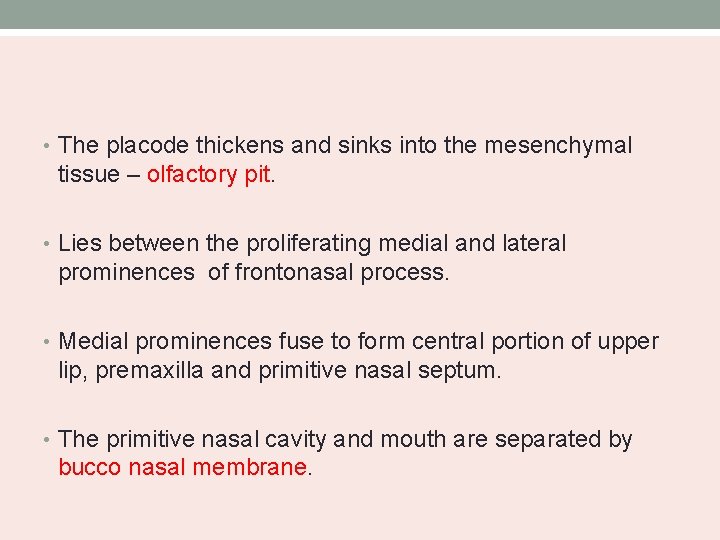

• The placode thickens and sinks into the mesenchymal tissue – olfactory pit. • Lies between the proliferating medial and lateral prominences of frontonasal process. • Medial prominences fuse to form central portion of upper lip, premaxilla and primitive nasal septum. • The primitive nasal cavity and mouth are separated by bucco nasal membrane.